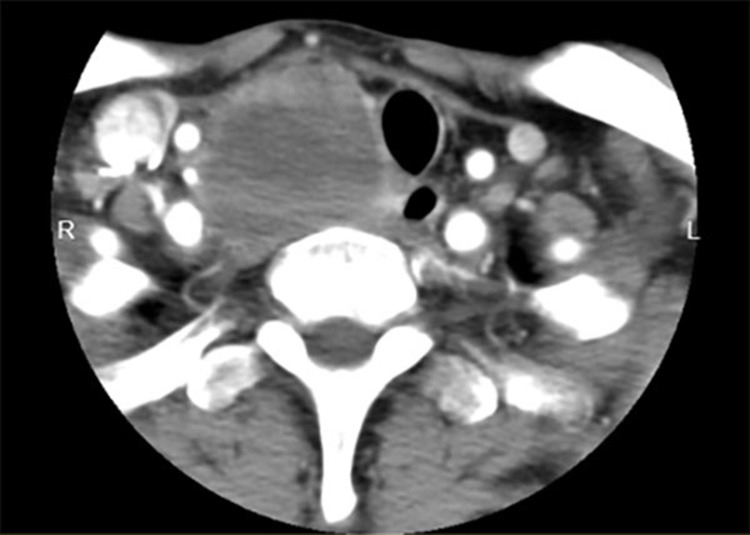

Case presentation: A 63-year-old male with a long-standing history of hepatitis B-related liver cirrhosis and a recent diagnosis of hepatocellular carcinoma presented with a rapidly enlarging painful right-sided thyroid mass associated with swelling but no systemic symptoms such as fever or dysphonia. This prompted a thorough diagnostic workup. Enhanced neck scans indicated a mass potentially originating from the thyroid with tracheal compression, yet crucially, there was no evidence of lung involvement based on the chest CT. Despite the rarity of liver-to-thyroid metastasis, the patient's multifaceted medical history warranted a broad differential diagnosis.